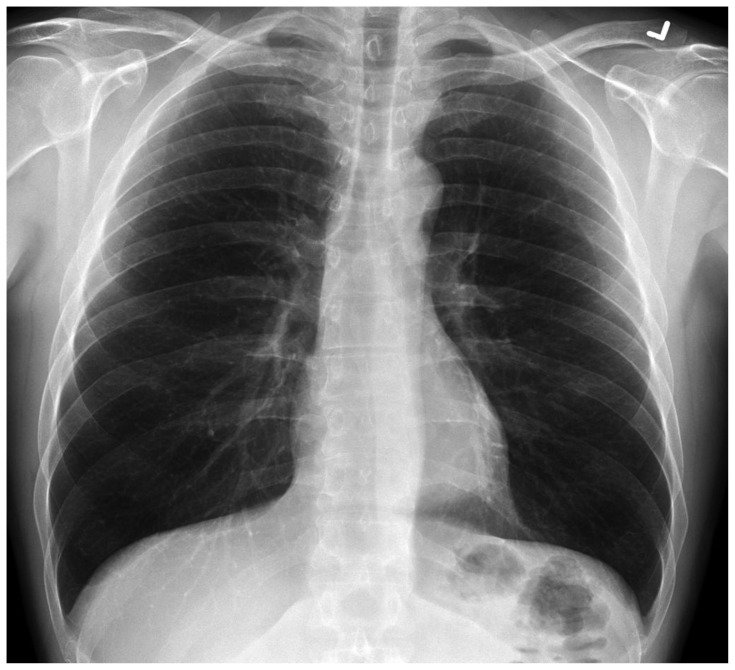

Abstract Image